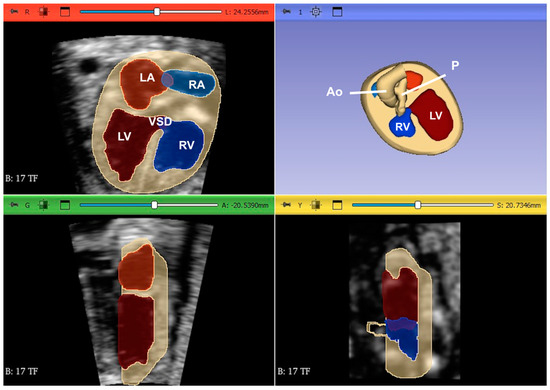

- Nieblas, C.O.; Bravo-Valenzuela, N.J.; Araujo Júnior, E.; Werner, H. Fetal transposition of the great arteries: 3D virtual and physical models from ultrasound datasets. Int. J. Cardiovasc. Imaging 2024, 40, 1157–1158. [Google Scholar] [CrossRef]